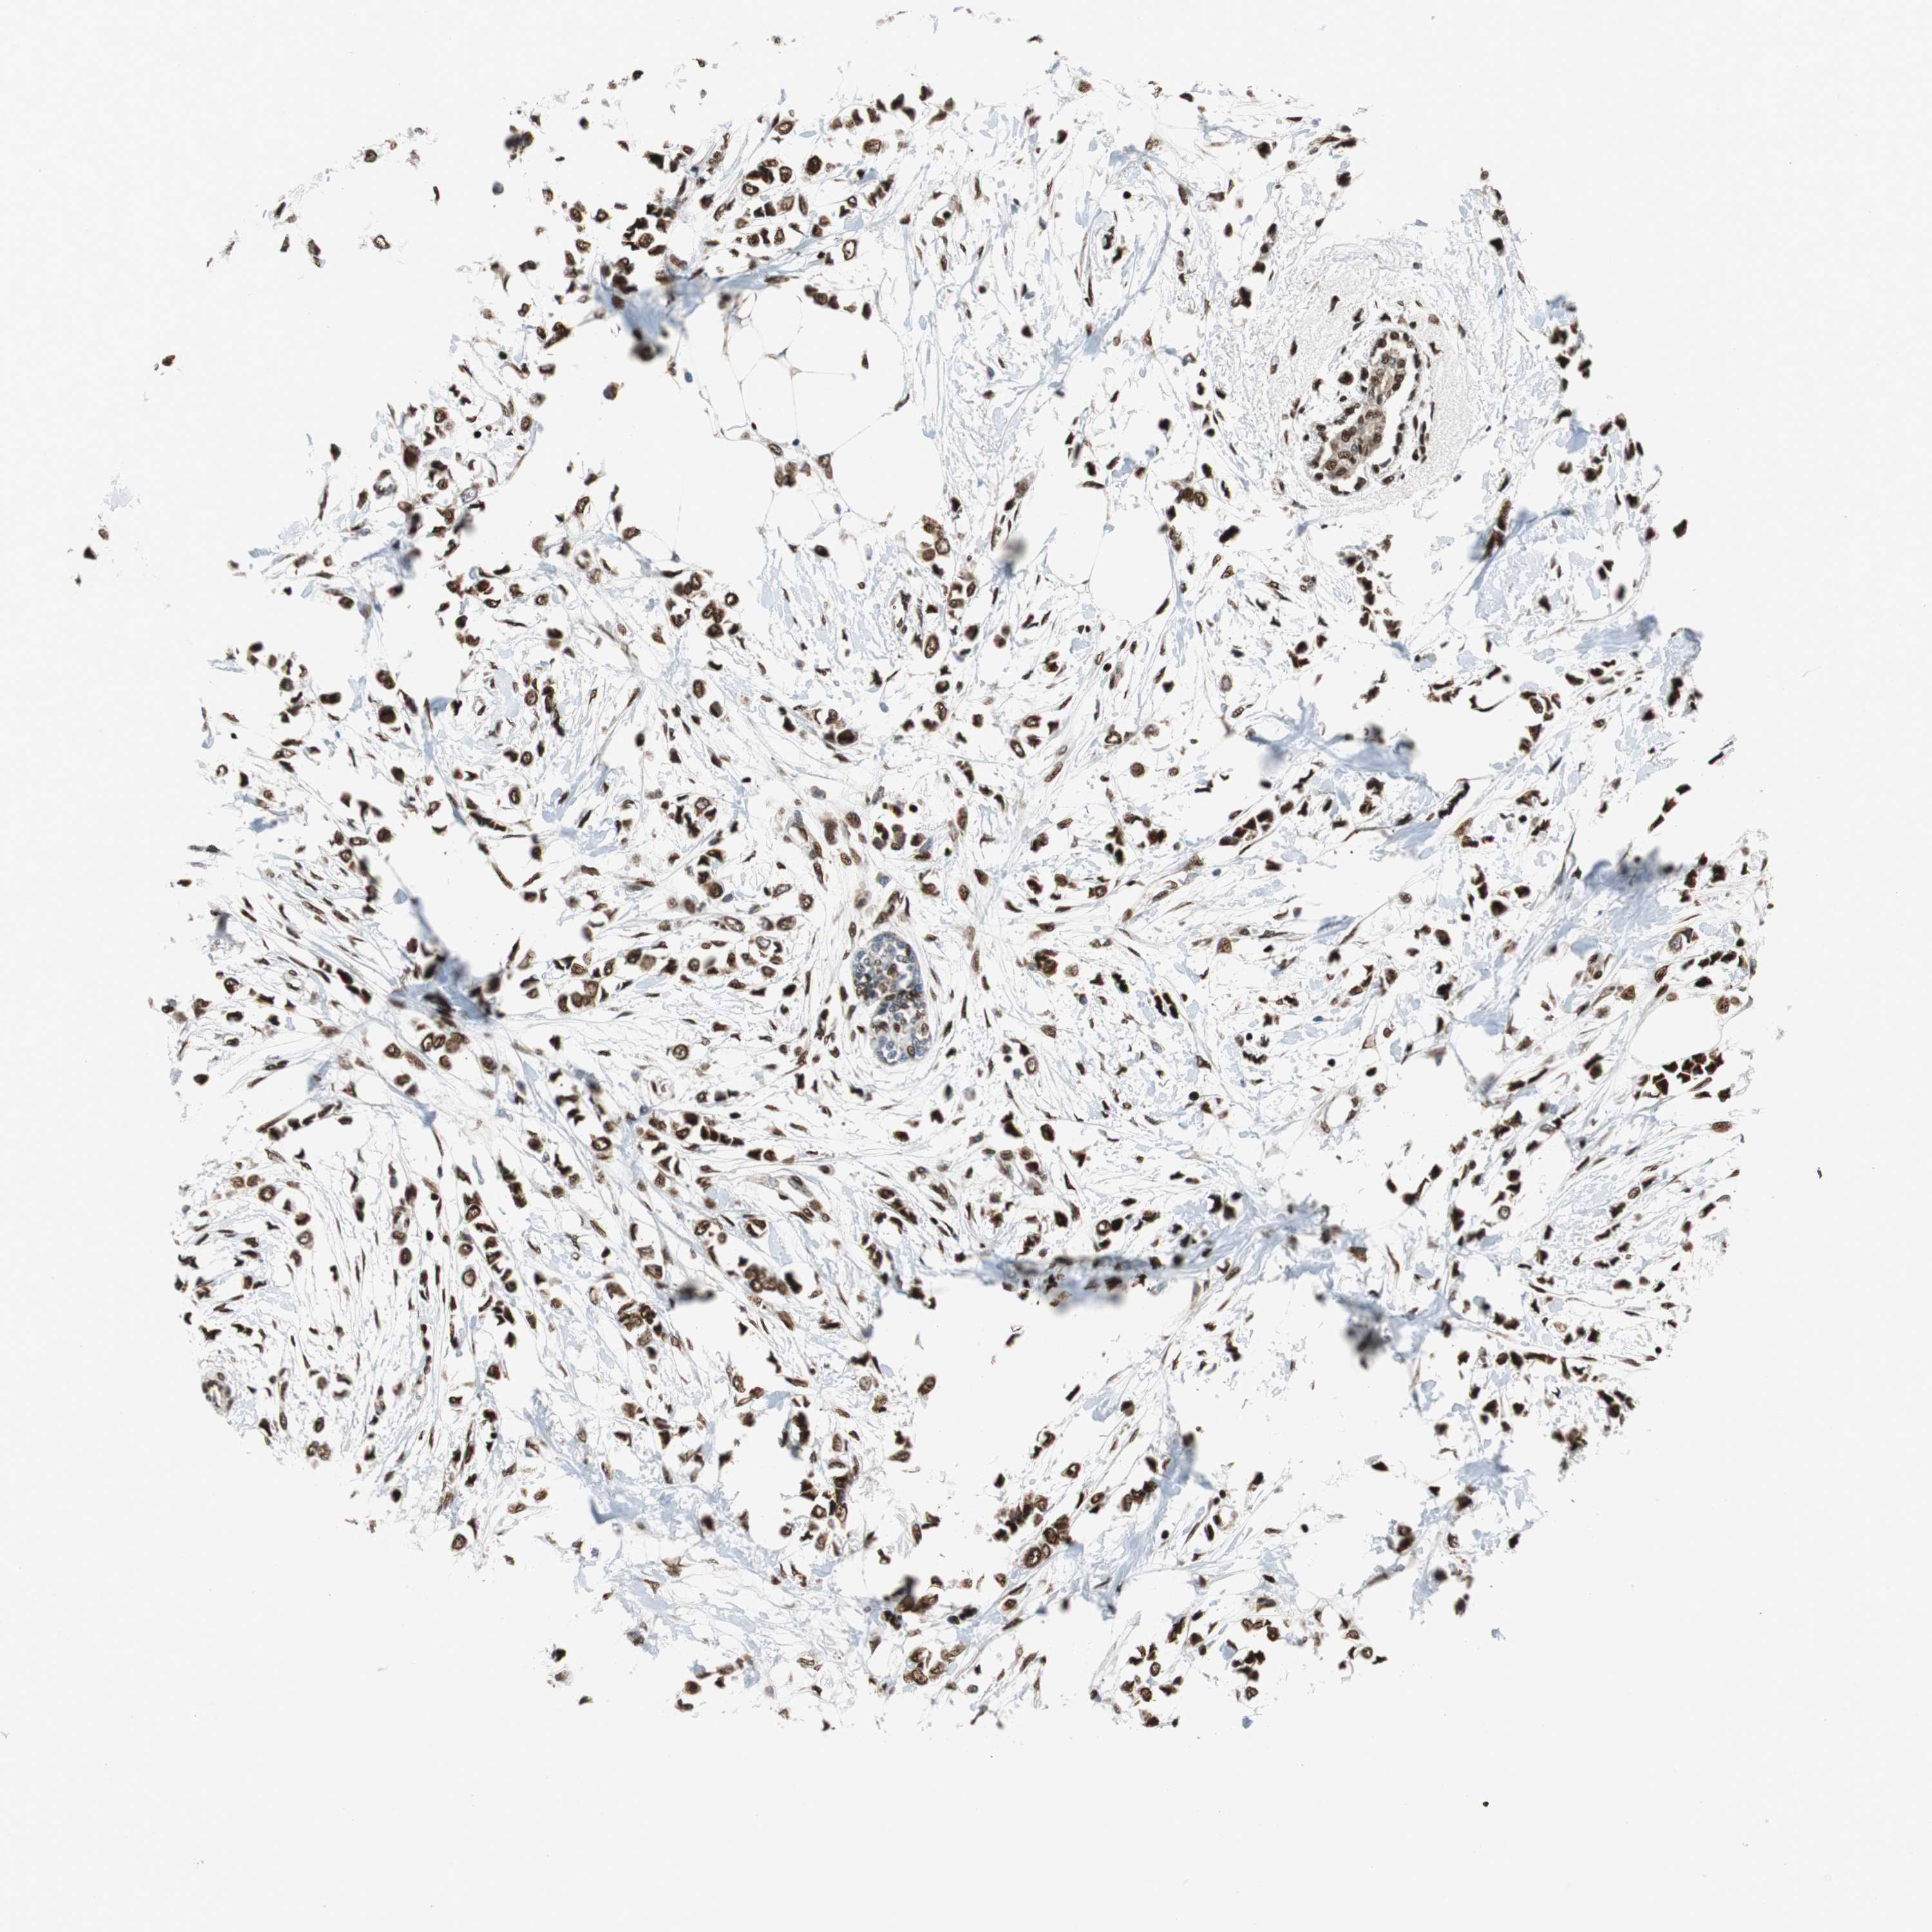

BRCA TCGA BRCA VALIDATION PROTEIN EXPRESSION

ANTIBODIES

AND

VALIDATION